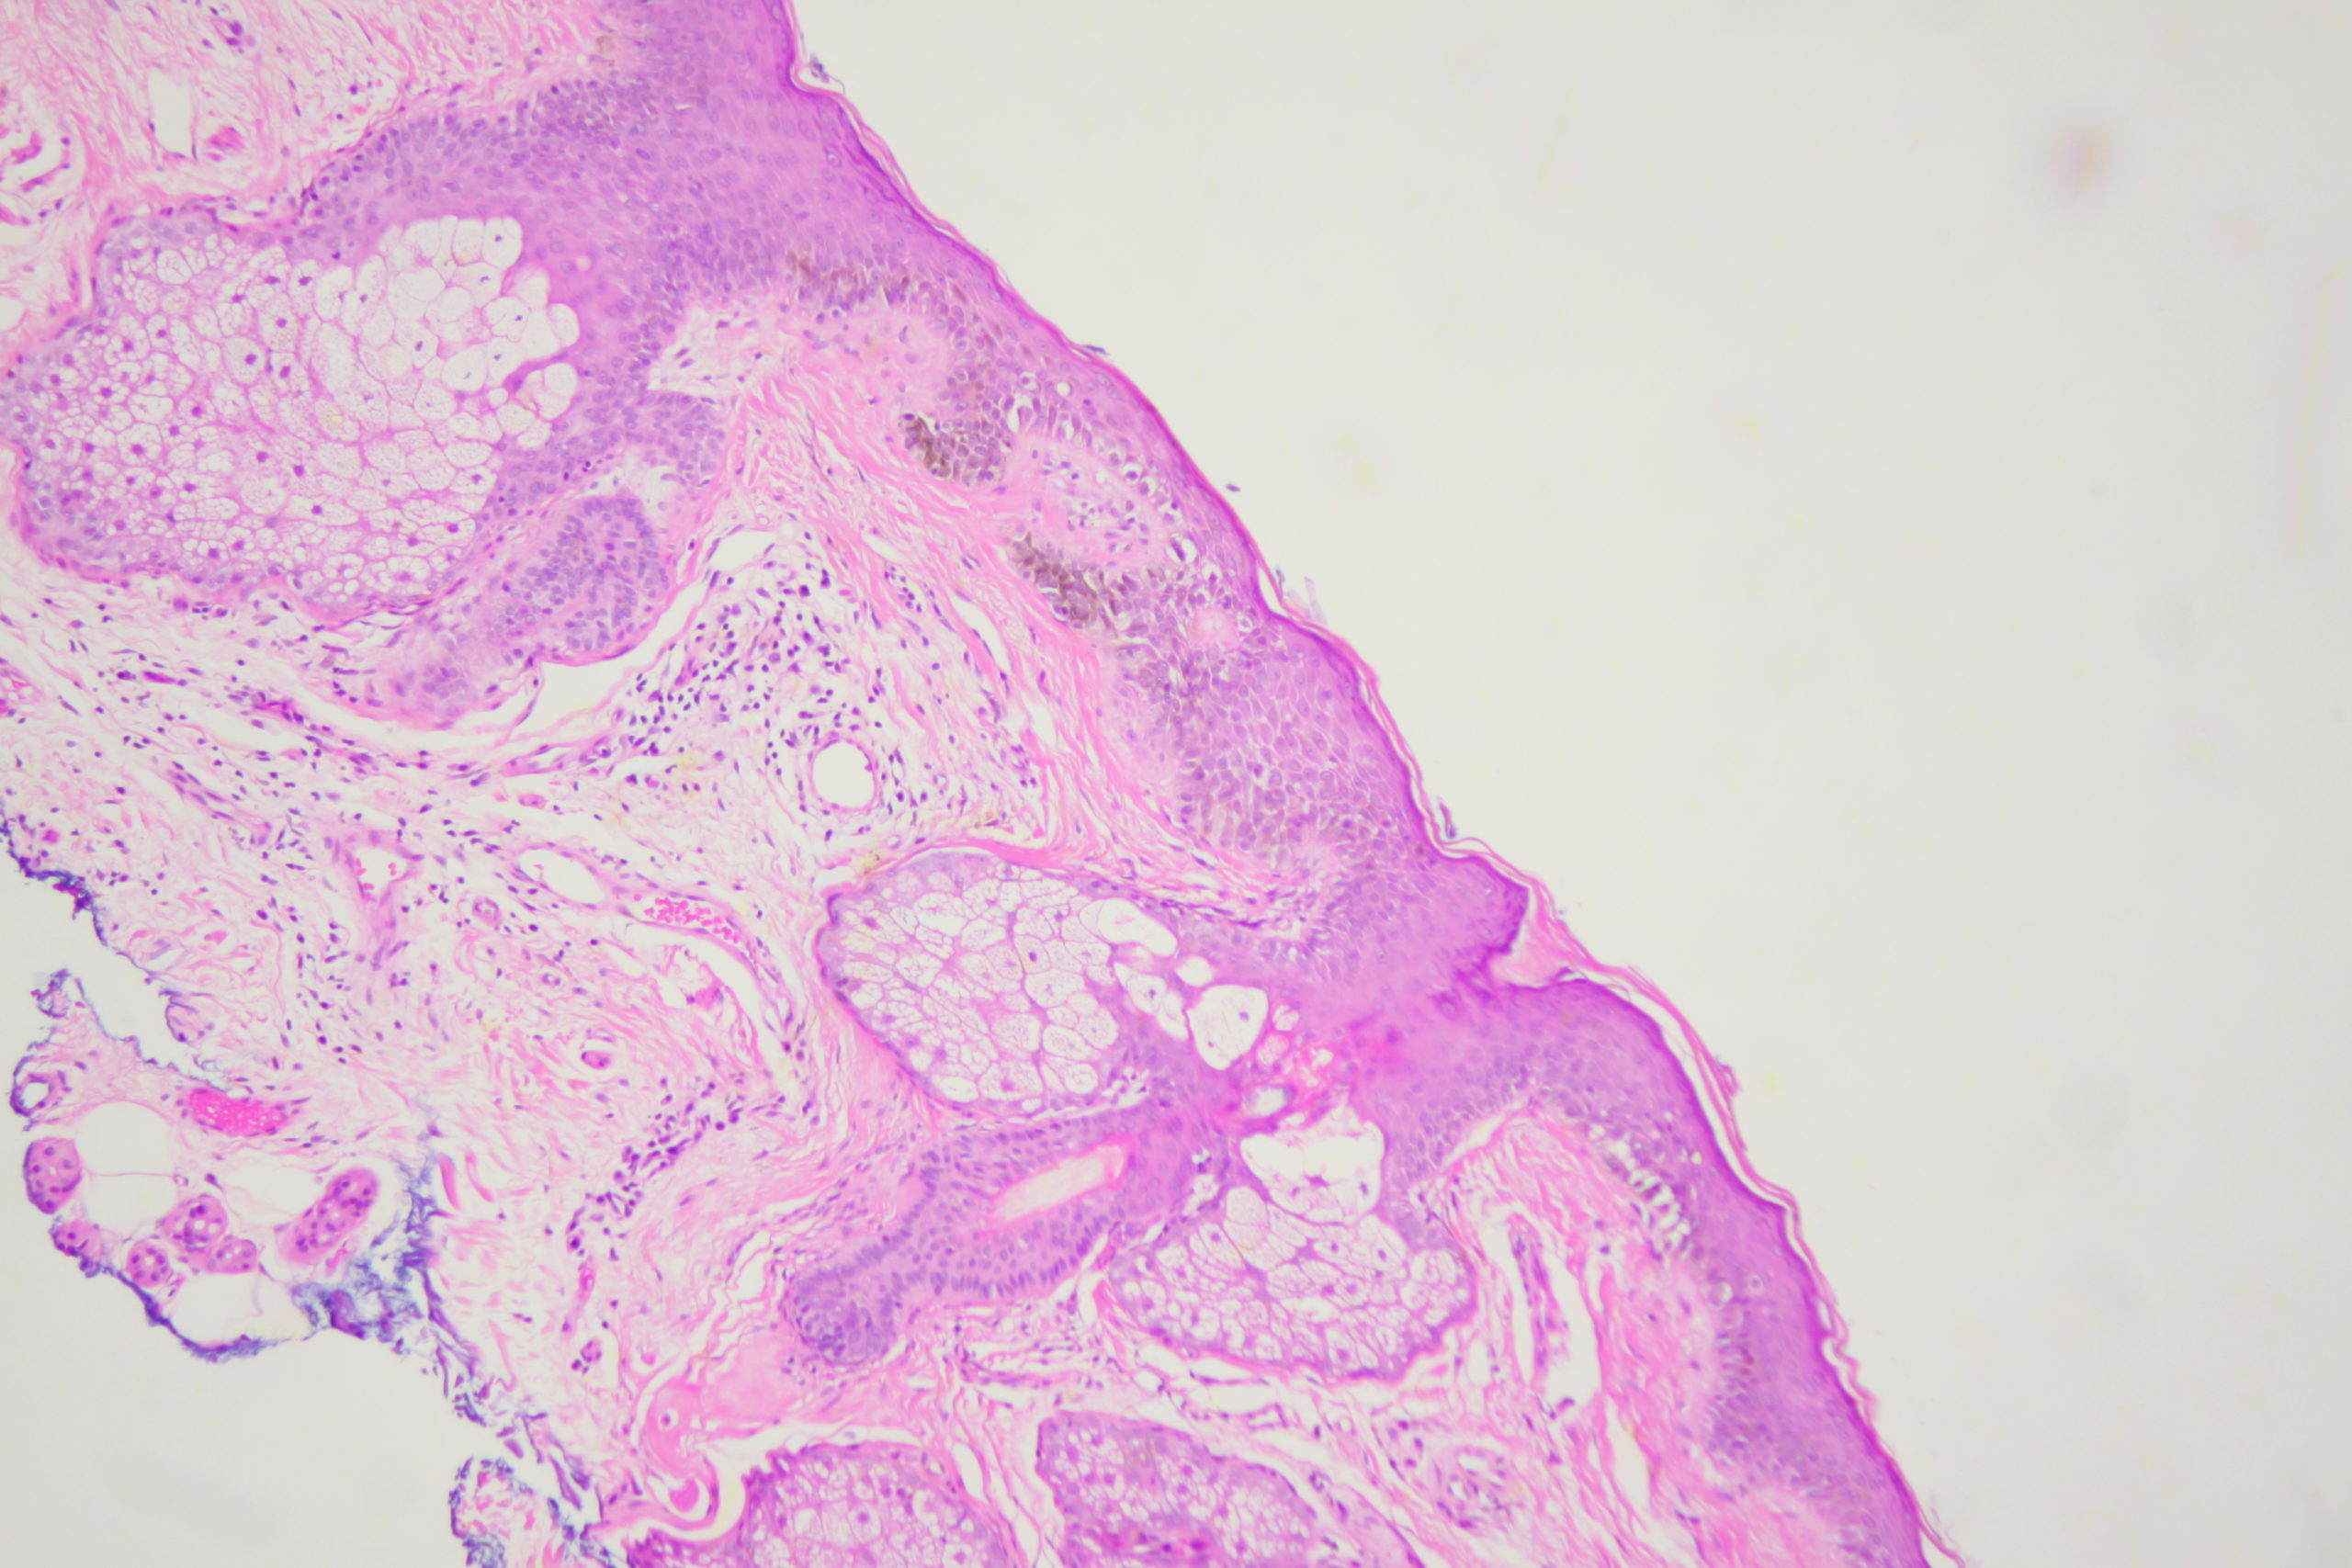

Image Number #3803 (Lentigo Maligna)

Site: Cheek

Diagnosis: Lentigo Maligna

Sex: M

Age: 65

A pigmented lesion on the cheek that has slowly been increasing in size over several years. Male aged 65. Smooth surface.

Dermatoscopy shows pigment dots and pigment around follicles as grey circles. PRAME and Sox 10 showed atypical melanocytes along the DEJ extending into and down follicles with localised upward pagetoid spread. Early Lentigo maligna / Superficial intraepidermal melanoma.